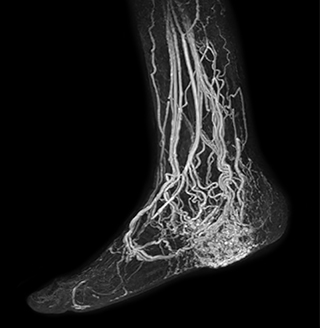

Another example is the foot examination for diabetic patients, which has improved dramatically. “The forefoot is generally difficult to image with MRI because of the inhomogeneities that the toes create – it’s hard to obtain good fat saturation in that area. Here, mDIXON made a huge difference right away, we obtain much better image quality,” Dr. Peña says. “Using mDIXON, Compressed SENSE and the dS FootAnkle coil, we have been able to reduce the scan time, so that we can now also include an additional 3D STIR sequence to visualize both arteries and veins in the foot.”

Avila adds: “In addition, since most of these patients are in a significant amount of pain, it’s important to perform the examination as quickly as possible. With Compressed SENSE and mDIXON we have been able to reduce the scan time from about 45 minutes to just 15 minutes. Not only does this improve patient comfort, we see that it also helps us acquire images without motion artifacts, which is critical to making a confident diagnosis.”